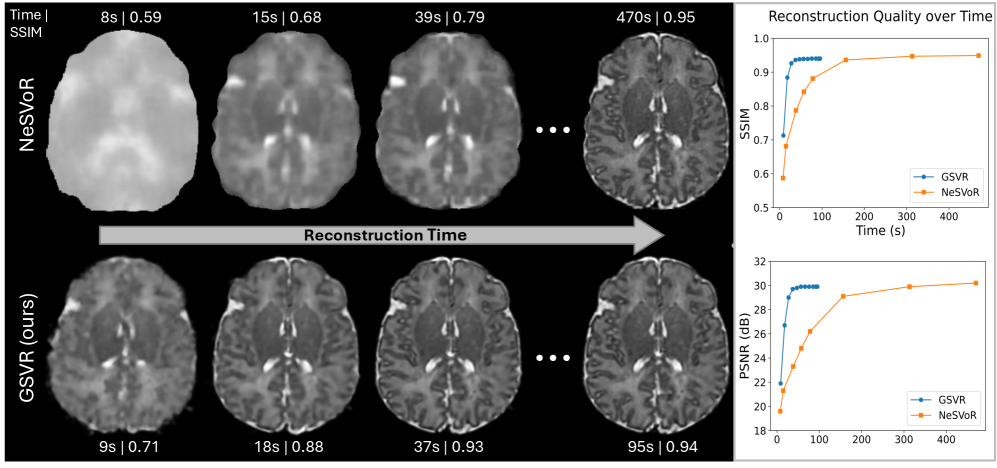

Efficiency. We demonstrate reconstruction speed-ups of factor compared to INR baselines on neonatal data, with convergence often reached in under 30 seconds, facilitating preview reconstructions during scan-time (\figurereffig:convergence).

Quantitative Evaluation on Simulated Data: Table LABEL:tab:sim_results summarizes performance on 10 simulated subjects. Our Gaussian-based SVR (GSVR) matches the state-of-the-art NeSVoR across all metrics (PSNR , SSIM ) without external slice pre-alignment, demonstrating robust internal motion correction. SVRTK degrades significantly ( dB) due to sensitivity to large motion corruption (see Appendix \figurereffig:sim_data_comparison). Critically, GSVR completes reconstruction in just s, a and speed-up over NeSVoR (s) and SVRTK (s), respectively. As shown in \figurereffig:convergence, our Gaussian representation with analytic PSF enables rapid convergence, yielding usable previews (SSIM ) in under 20 seconds.